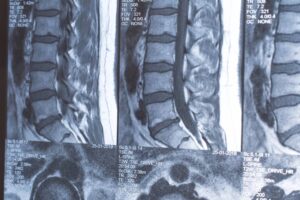

We start with a thorough examination. We need to know exactly which disc is herniated and how badly. If you don’t have recent MRI results, we might order one. MRI is the gold standard for seeing disc problems. X-rays show bones but not soft tissue like discs.

If you already have an MRI from your doctor, bring it with you. If you don’t have one and we think it’s necessary based on your examination, we’ll order one. MRI shows the soft tissue—the discs, nerves, and ligaments—that X-rays can’t see.

Once we know what’s wrong, we explain it to you in plain English. We show you on the images. We tell you how bad it is and what treatment will look like. We discuss how long recovery typically takes and what you need to do at home to help the healing process.